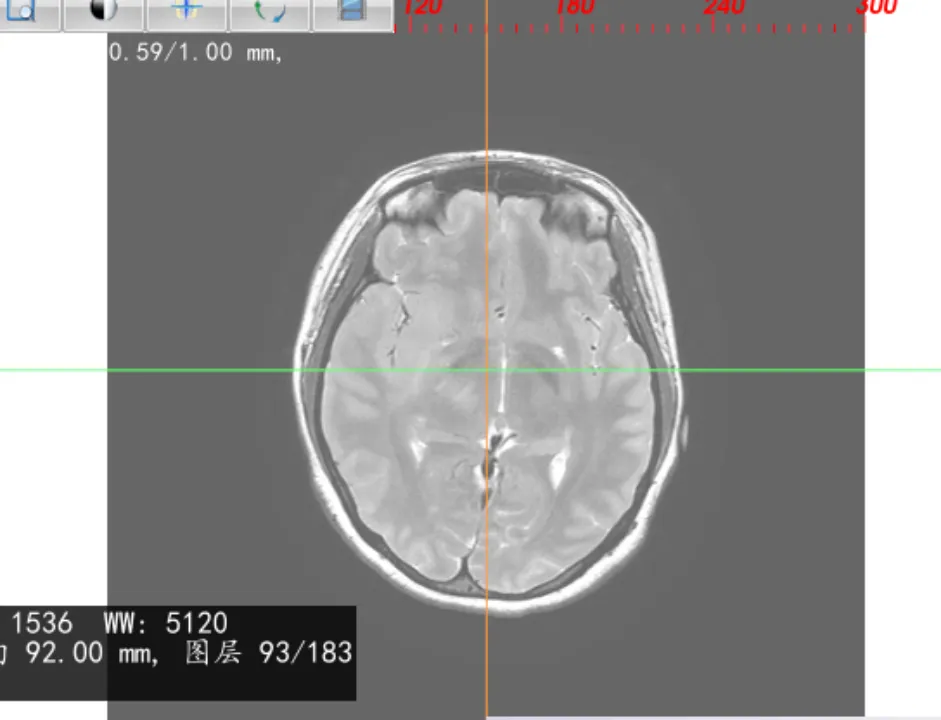

图像融合

导入多个序列,可对图像进行一键融合,生成融合序列,如:进行CT、磁共振融合,设定融合比例,可对CT或磁共振显示的权重进行调整。

0% 50% 100%